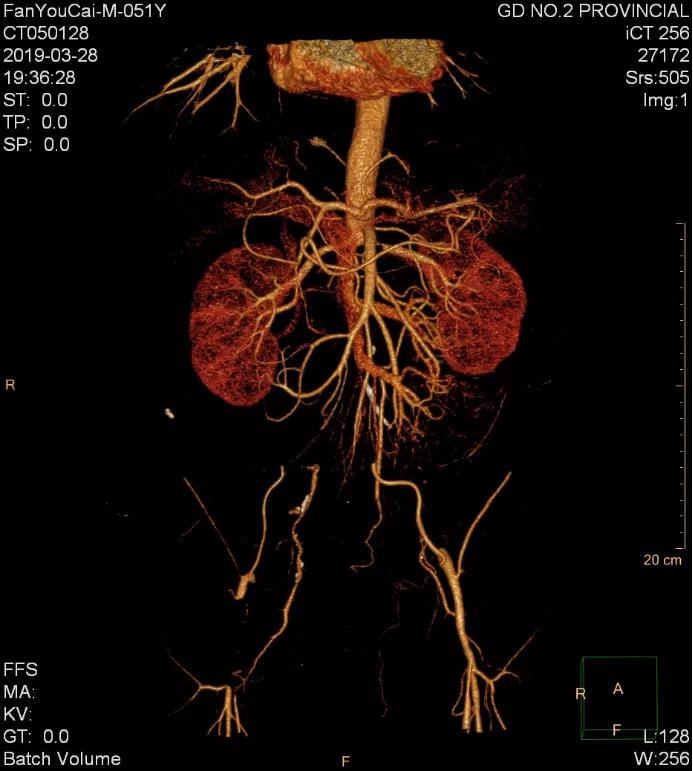

经过系统检查,老樊被确诊为肾下腹主动脉闭塞症。

“根据影像显示,患者主动脉自肾动脉以下完全闭塞,双侧髂动脉完全闭塞,右侧股动脉起始部完全闭塞,双下肢缺血严重,随时面临截肢的风险。”李立恒说。